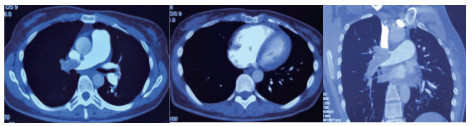

例4 62岁,女性,主诉“活动后气短20 d,加重1 d伴晕厥1次”。患者入院20 d前上近20级台阶后感气促,休息后缓解,未重视。入院前1 d,突发晕厥伴有轻微活动后明显的呼吸困难。既往:左下肢静脉曲张病史3~4年;入院40 d前患者左足跖骨骨折,接受外固定,尚未影响日常活动,未接受抗凝治疗;发现血小板减少数年(血小板维持5.5~8.6 g/L,末次于一年前血小板85 G/L),未明确原因及治疗;血气分析提示pH 7.447,PaCO2 32.2 mmHg,PaO2 85.3 mmHg,SaO2 96.8%;D-Dimer 1 947 ng/mL;FDP 22.84 μg/mL,FBG 2.05 g/L;PLT 51G/L;cTnI 0.52 ng/mL,BNP 299 pg/mL;ALT 318 U/L,AST 300 U/L,CREA 74.8 μmol/L,血Na+、K+、Cl-:正常范围;UCG提示:右心大,肺动脉主干轻度增宽(28 mm),三尖瓣反流(重度),反流面积13.7 cm2,TI法估计SPAP为30 mmHg、左室舒末内径35 mm、左室舒张功能受限(E/A 1:1.5)、未见节段性室壁运动障碍;双下肢静脉超声提示左侧腘静脉不完全血栓。心电图(图 12所示)提示窦性心动过速、SⅠQⅢTⅢ;CTPA显示肺动脉分叉处及双肺亚段充盈缺损(图 13所示)。

| 图 13 入院时CTPA结果显示肺动脉分叉处及双肺亚段充盈缺损 |

入院查体:神志清楚,体温36.5℃,血压120/70 mmHg,脉率110次/min,呼吸22~26次/min,指氧饱和度93%(安静,空气氧),未见乏氧征。双肺呼吸音清,未闻及干湿性啰音,心率110次/min,律齐,P2 > A2,心界无扩大,无杂音,腹软,无压痛,肠鸣音正常。神经系统未见异常。左下肢膝关节以下可见静脉曲张,双下肢无浮肿。入院诊断:急性肺血栓栓塞症(中高危);左下肢静脉曲张并血栓形成;血小板减少症;肝功能不全。处理方法及原因:患者中年,日常生活质量高;入院20 d前虽有症状,但入院1 d前明显加重并出现晕厥发作;两次D-Dimer检查均<2 000 ng/mL,与CTPA显示的血栓负荷不匹配。入院后连续两次检测血小板均低于正常(51~77 g/L)。因考虑病史较长但近期有加重、血小板低等原因系统溶栓治疗出血风险较大,所以给予导管介入碎栓并行肺动脉内溶栓治疗(r-tPA 20 mg)。溶栓2 h后患者症状明显缓解,复查D-Dimer 12 560 ng/mL,序贯肝素抗凝并复查CTPA提示原有血栓明显消失(图 14所示)。

| 图 14 介入溶栓后患者CTPA结果提示明显改善 |

患者特点及再灌注治疗时机及方式选择:患者病程20 d,但是入院前1 d呼吸困难加重同时伴有晕厥,提示1 d内有明确的新的血栓脱落导致的一过性脑缺血。理论上讲,如果纤溶功能正常的话,CTPA显示的血栓负荷与D-Dimer具有一定的匹配性,而本例患者连续两次检测并未发现这种匹配的特点,分析原因有两种可能:①原有主肺动脉干血栓负荷较大,近期虽然有新的血栓脱落,但新鲜血栓的负荷量不足以大到D-Dimer明显升高的地步;②主干血栓为近期一次脱落而成,但是患者有存在继发纤溶低下的可能,同样表现为较低的D-Dimer水平。如果存在继发纤溶功能低下的话,难以避免单纯抗凝治疗后栓塞性肺动脉高压的风险。我们决定给予介入下的碎栓并肺动脉内溶栓治疗是考虑原有血栓阻塞左右肺动脉主干,很难代偿新鲜血栓的再次脱落。更重要的是,CTPA提示肺动脉主干的骑跨血栓密度尚不支持陈旧血栓。溶栓后CTPA结果也验证了对CTPA结果解读的正确。本例患者另一个特点D-Dimer水平与血栓负荷不成比例的另一个依据是凝血机制检测提示纤溶系统异常,PAI-1活性超过正常3倍,证实了最初的判断。